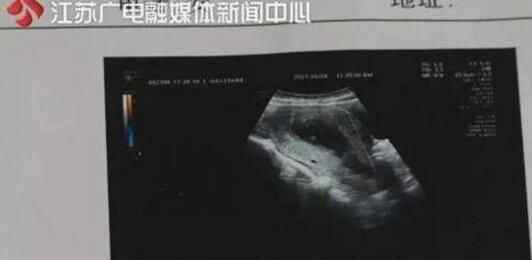

2017年9月,郭女士在连云港市第一人民医院产科生完孩子后,腹腔一直疼痛难忍,接连三个月的消炎治疗都未见好转。可是某天洗澡时,竟意外从身体里扯出一块发臭的纱布。原来,郭女士分娩时出现了大出血的情况,医务人员采取紧急止血措施,在她身体里放了很多止血纱布。此后,婴儿顺产,郭女士在医院住院三天后,正常出院。但是,郭女士产后恢复非常不理想,腹腔部位一直疼痛难忍,不时会有脓水从下身流出。